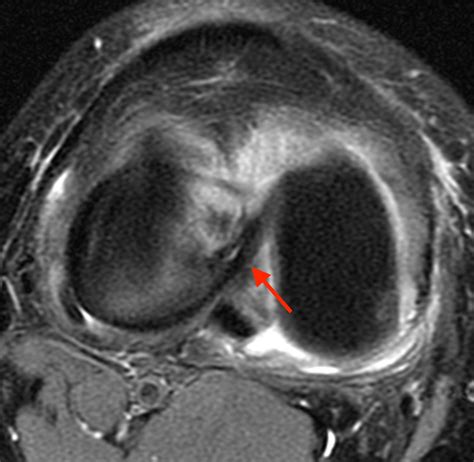

A Bucket Handle Injury is a specific type of meniscal tear that occurs in the knee. The meniscus is a C-shaped piece of cartilage that acts as a shock absorber between the thighbone (femur) and the shinbone (tibia). When a tear occurs in a way that the inner portion of the meniscus flips up into the joint, it is called a bucket handle tear because it resembles the handle of a bucket.

• MRI (Magnetic Resonance Imaging): To provide detailed images of the soft tissues, including the meniscus, to confirm the diagnosis.